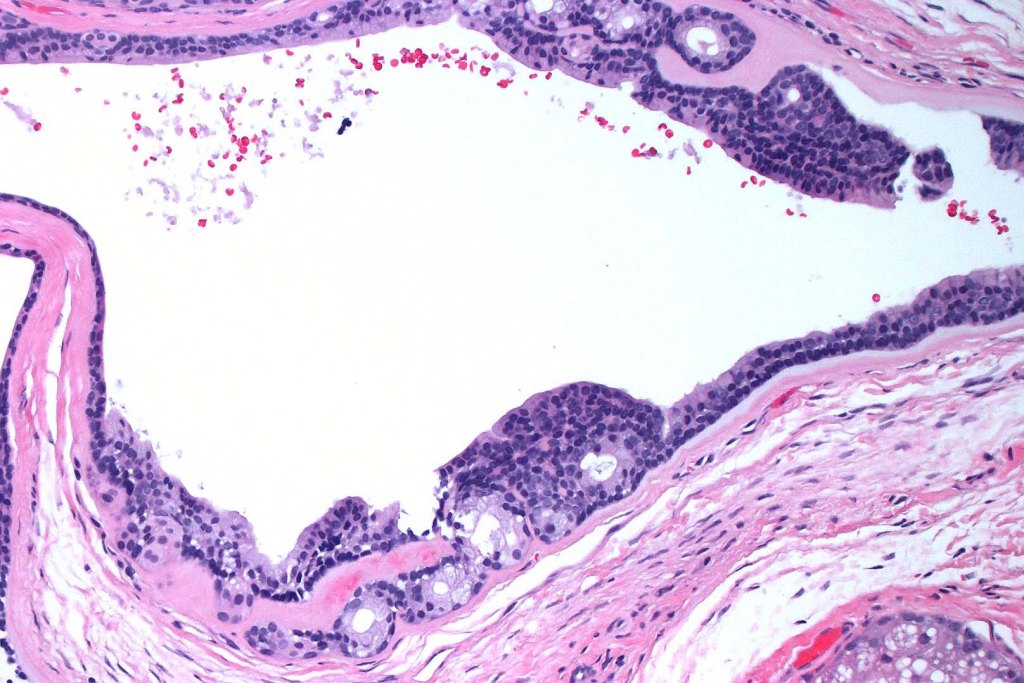

•Pseudo-encapsulated unilocular or multilocular

•Outer myoepithelial cells & inner layer of columnar cells with eosinophilic cytoplasm showing decapitation secretion

•Adenomatous/papillary component (cystadenoma)